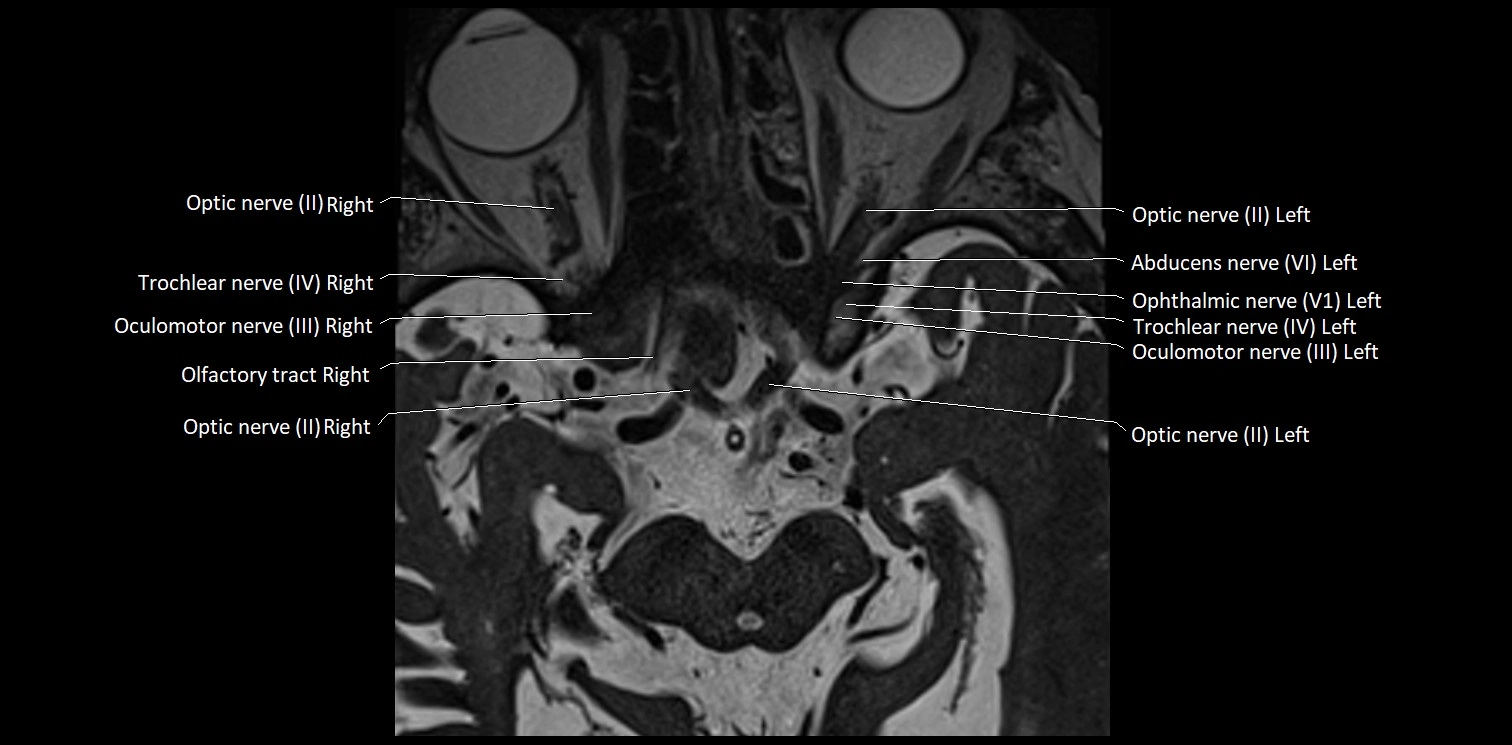

MRI Appearance

• The abducens nerve is a small, thin, linear structure

• Best visualized on high-resolution T2-weighted 3D MRI sequences (e.g., FIESTA or CISS)

• Seen as a hypointense (dark) line running from the brainstem at the pontomedullary junction, traversing the prepontine cistern, and entering Dorello’s canal under the petrosphenoidal ligament, then into the cavernous sinus, and finally the orbit

• May be challenging to visualize in standard MRI due to its small size

• Pathology may be inferred by absence, displacement, or enhancement of the nerve

MRI images

image